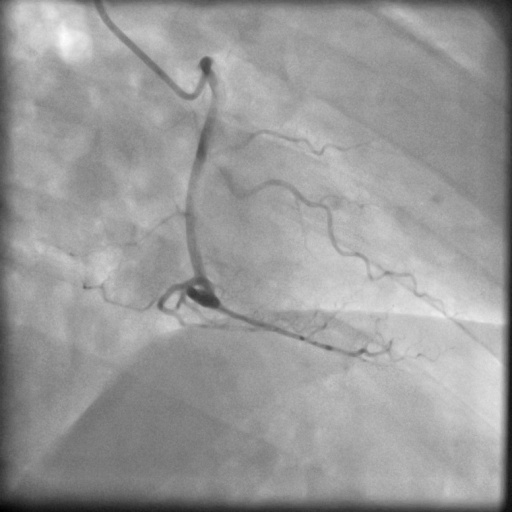

4.1 XACV Dataset

We collect 111 complete records of coronary artery X-ray videos, encompassing the injection, flow through the blood vessels around the heart, and dissipation of the contrast agent. Subsequently, we establish the XACV (X-ray Angiography Coronary Video) dataset. Each video consists of varying numbers of high-resolution coronary artery X-ray images. We invite experienced radiologists to annotate the vascular regions, focusing on one or two frames where the contrast agent is most prominent in each video. The XCAD dataset contains only a single image, and the CADICA video dataset does not provide corresponding ground truth. Therefore, in the following experiments, we conduct all the analyses on our collected XACV dataset and the corresponding GT for each sequence. In Figure 5, we show that compared to other publicly available datasets, XCAD [33] and CADICA [19], our dataset exhibits finer annotations in the vascular regions, providing an advantage for future related tasks. The development and use of our dataset have been approved by our institution’s IRB.